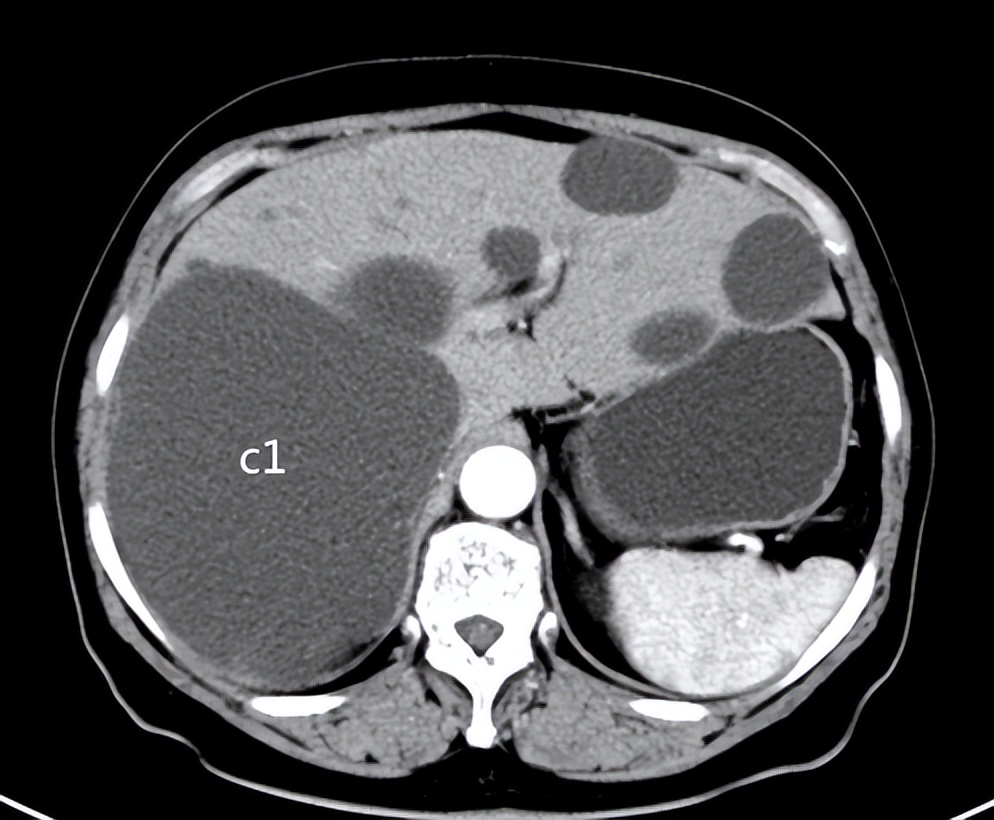

CT:单个最大者>15cm

患者女性,50岁,多年前健康查体发现多发肝囊肿,最大者直径4cm。一年来感觉右上腹胀满,疼痛,食欲减退,来院检查,CT/超声提示:肝内多发肝囊肿,最大者直径>15cm。患者住院行:介入超声肝囊肿硬化治疗术。

大于8cm的肝囊肿定义为大囊肿,本病例直径大于15cm。先采用置管引流术和隔日进行了两次注射硬化剂治疗,主要目的为了引流完全,防止囊肿过大一次抽吸囊液不完全,分次注射硬化剂是考虑到囊肿过大、一次注射硬化剂量有限(囊内单次无水乙醇量不宜超过100mL),担心硬化剂不能与囊壁充分接触,影响治疗效果。因为考虑囊壁上引流管孔较大,为了防止无水乙醇顺着引流管孔流出囊腔引起酒精性腹膜炎,治疗结束后未在囊腔内保留无水乙醇。其他囊肿硬化采用常规单次硬化治疗术。因考虑到病人身体承受能力问题,一次治疗了三个囊肿,未对其他小一点的囊肿进行治疗,留作下一次治疗。